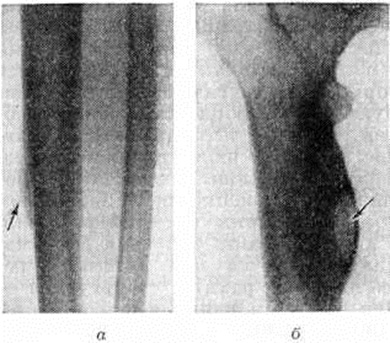

ОстеопериоститОстеопериостит (osteoperiostitis; греческий osteon кость + периостит) — воспалительный процесс в кости с преимущественным поражением надкостницы; термином «остеопериостит» пользуются главным образом рентгенологи для обозначения определённого рентгенологического симптомокомплекса, так как клинически остеопериостит чаще проявляется и течёт, как остеомиелит. Возбудителями Остеопериостит могут быть разнообразные представители гнойной и специфической микрофлоры. Поэтому он встречается при гематогенном и посттравматическом остеомиелите (смотри полный свод знаний), костном туберкулёзе (смотри полный свод знаний: Туберкулёз внелёгочный, туберкулёз костей и суставов) сифилисе (смотри полный свод знаний), склерозирующем остеомиелите Гарре, абсцессах Броди (смотри полный свод знаний: Броди абсцесс), гонорейных, бруцеллезных, брюшнотифозных и других воспалительных процессах в костях. Описаны случаи актиномикозного Остеопериостит Остеопериостит возникает вследствие перехода процесса с мягких тканей на кость, что чаще бывает при посттравматическом остеомиелите, либо, наоборот, начавшись в костном мозге, воспаление распространяется на надкостницу. Тяжёлые формы Остеопериостит наблюдаются после инфицированных открытых переломов и ложных суставов. Гистологический и бактериологические исследование подтверждает инфекционно-воспалительный генез заболевания. Уже при ограниченном Остеопериостит возникает отслойка надкостницы, что нарушает связь кости с мягкими тканями и ухудшает трофику поражённой кости, способствуя образованию секвестров (смотри полный свод знаний: Секвестр, секвестрация). Рентгенологические распознавание Остеопериостит, возникающего при различных воспалительных заболеваниях или травматических повреждениях кости, основано на обнаружении и изучении происходящих при этом процессе разрушений костного вещества и репаративных изменений. Деструктивные явления относятся в основном к корковому веществу кости, репаративные — преимущественно к надкостнице и в меньшей степени к эндосту. Деструкция костного вещества при несомненных клинических и анатомических признаках воспалительного процесса рентгенологически обнаруживается только при достаточной степени развития этого процесса, а репаративные изменения — лишь при обызвествлении образуемого надкостницей остеоидного вещества. Наиболее показательна рентгенологическое картина неспецифического Остеопериостит длинных трубчатых костей. Вначале появляется сопутствующая корковому веществу полоска тени обызвествленных периостальных наложений, отделённая от наружной поверхности коркового вещества кости тонким слоем необызвествленной патологический ткани. Между периостальными обызвествлёнными наложениями и корковым веществом остаётся прозрачная для рентгеновских лучей полоска (рисунок 1, а). По мере развития патологический процесса обызвествлённые массы, постепенно утолщаясь, сливаются с подлежащей костью. Слившиеся с компактным веществом периостальные наложения создают картину асимметричного утолщения кости. В глубине этого утолщения виден очаг деструкции различных размеров (рисунок 1, б), являющийся центром всего патологически изменённого участка кости; иногда в центре деструктивного фокуса можно обнаружить небольшой костный секвестр. Выпуклая кнаружи поверхность кости в месте утолщения имеет гладкие или шероховатые очертания. При корковом абсцессе определяется деструктивный очаг. При гуммозном Остеопериостит рентгенологическое картина отличается несколько иной последовательностью изменений. Оссифицированные периостальные наложения являются следствием развития микроскопических периваскулярных инфильтратов в надкостнице, поэтому макроскопически уловимая деструкция костного вещества вначале обычно отсутствует. Деструкция выявляется, как правило, позднее, когда происходит распад вновь образовавшегося костного вещества из-за присущего гуммозному процессу свойства обязательно проходить эту стадию хронического воспалительного процесса. Возникающий при этом деструктивный очаг обычно имеет вид краевого дефекта (рисунок 2). В трудных случаях при дифференциальной диагностике гуммозного Остеопериостит с корковым абсцессом наличие кортикального секвестра даже при краевом деструктивном дефекте говорит в пользу неспецифического, а не сифилитического Остеопериостит |